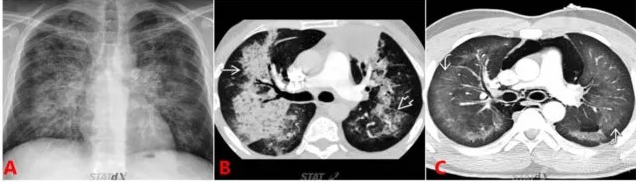

圖 6 心源性肺水腫典型表現(xiàn):蝶形影/蝙蝠翼樣表現(xiàn)

圖 6A 顯示的是肺水腫患者的普通胸片,可見雙肺紋理明顯增多,以肺門為中心的彌漫性滲出影。近胸膜處不明顯,即蝶形滲出,中心大于外周。

圖 6B 為肺水腫患者的 CT 顯像,同樣表現(xiàn)為中心大于外周的彌漫滲出,稱之為蝙蝠翼征。

圖 6C 可見雙肺彌漫廣泛滲出,但近胸膜處滲出影明顯多于肺門周圍,即外周大于中心,該片為過量使用可卡因?qū)е录毙苑嗡[。